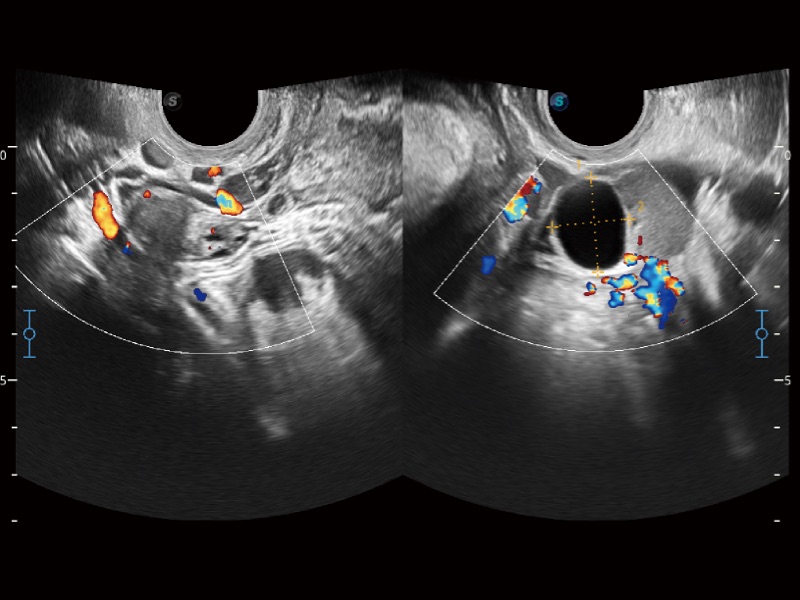

• SR Flow

Como nueva tecnología innovadora, SR Flow mejora la capacidad de detectar señales de flujo de baja velocidad. También mejora la resolución espacial y sortea el sobreflujo para presentar a los usuarios información hemodinámica real.

Ovarios bilaterales

Adhesión intrauterina